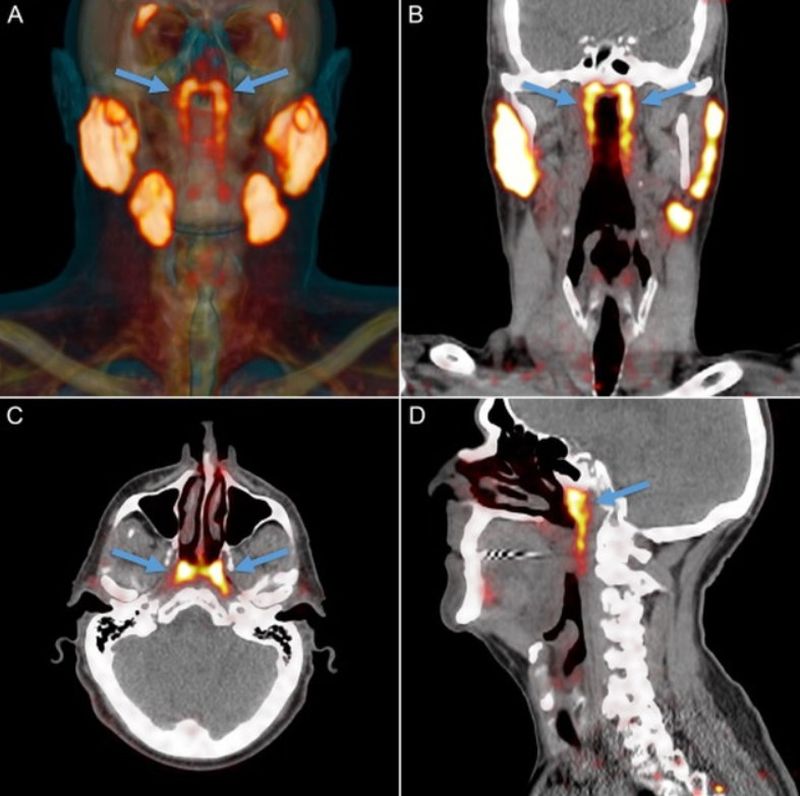

Ei au folosit tomografie cu emisie de pozitroni/tomografie computerizată cu scanări cu liganzi antigen de membrană specifici de prostată (PSMA PET/CT), care s-au dovedit a fi o modalitate eficientă de urmărire a răspândirii cancerului de prostatată în întregul corp. Pacienților li se injectează glucoză radioactivă înainte de scanare, ceea ce evidențiază tumorile din interiorul pacientului prin strălucire.

În timpul folosirii acestei scanări la pacienți, echipa a observat că două zone ale capului s-au iluminat în mod neașteptat.

Pe măsură ce continuau să scaneze pacienții, au tot găsit aceeași zonă iluminată.

Astfel, s-a dovedit că cele 100 de persoane scanate avea puncte luminoase. Nu era o anomalie, ci un potențial organ nou.

Noua descoperire a fost descrisă în revista Radiotherapy and Oncology ca fiind un set de glande salivare, predominant glande mucoase, cu canale de drenare multiple, ce sunt poziționate în partea din

spate a nazofaringelui

„Oamenii au trei seturi de glande salivare mari, dar nu acolo. Din câte știam, singurele glande salivare sau mucoase din nazofaringe sunt microscopic mici și până la 1000 sunt răspândite uniform în toată mucoasa. Așa că, imaginați-vă surpriza noastră când le-am găsit” , a explicat autorul studiului și oncologul de radiații Wouter Vogel într-un comunicat, scrie playtech.ro

Echipa a reușit să-și confirme descoperirile, împreună cu colegii de la Amsterdam UMC, folosind cadavre și au numit acum cel mai nou organ al umanității „glande tubare”, referindu-se la locația lor. Ei sunt de părere că glandele ar putea fi o cauză a complicațiilor pentru pacienții care suferă de radiații, inclusiv disfagie (probleme la înghițire), iar cunoașterea lor ar putea ajuta oncologii să evite această zonă pentru a putea peveni potențialele complicații.